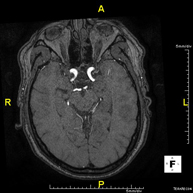

- Brain MRI (cranial)

This non-invasive diagnostic procedure uses an electromagnetic field and radio waves (from a transmitter and receiver) to acquire high-definition anatomical images of the brain. It is a radiation-free procedure. Indicated for: vascular problems, memory loss, epilepsy, headache, malformations, suspected tumour, meningitis.